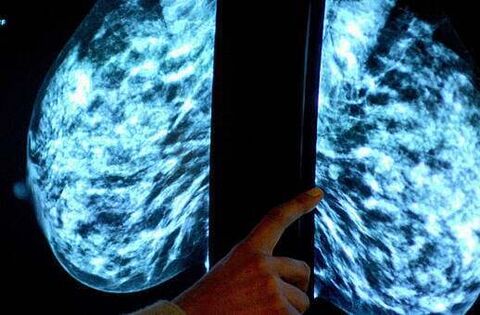

HSE breast cancer screening programme misses targets for past two years

The HSE's national screening service for breast cancer has missed targets for the past two years.

Over 75,000 women were not screened as intended under the BreastCheck programme.

BreastCheck is a free breast screening programme for those aged 50 to 69 years, usually around every two years.